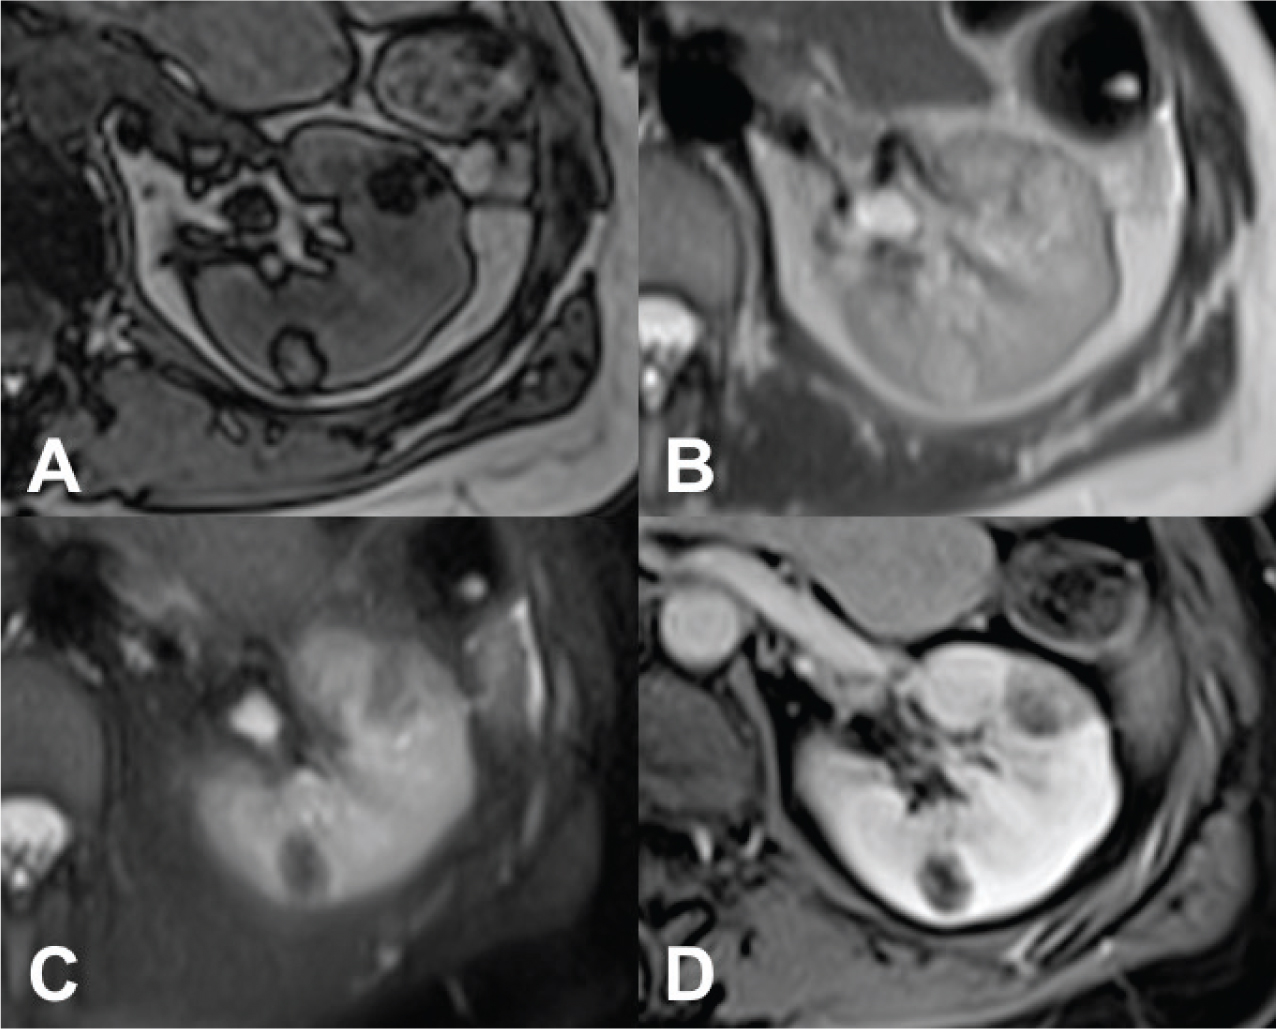

Fig 1

Figure 1. CT axial scan of the abdomen during venous phase of a 45-year-old woman with TS showing the presence of renal angiomyolipomatosis (A and B) and caliectasia at the level of the left upper calyceal group (A). Furthermore, a cystic lesion with solid peripheral tissue indissociable from the left inferior renal pole is evident (B). At the follow-up CT scan performed approximately 6 months later, the cystic lesion showed an increase of the solid component. Consequently, the patient underwent left nephrectomy and tumorectomy. Histological examination revealed the diagnosis of dedifferentiated liposarcoma.